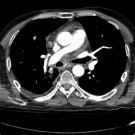

A 77-year-old man first presented to the emergency department (ED) due to hemoptysis and intermittent shortness of breath.